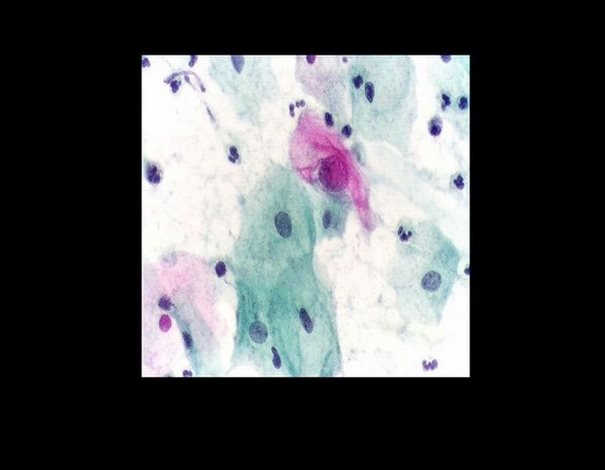

Η παρατήρηση του κολπικού επιχρίσματος και η εύρεση σε αυτό ατύπων κυττάρων, που αποπίπτουν από το νεόπλασμα του τραχήλου της μήτρας, τον οδήγησαν στην ανακάλυψη του Pap Test. Μια ανακάλυψη που άλλαξε αποφασιστικά τον μέχρι τότε τρόπο αντιμετώπισης του καρκίνου.

Αναζητά αν τα κατώτερα θηλαστικά έχουν περιοδικό κύκλο όπως τα ανώτερα. Παίρνει κολπικό επίχρισμα και ανακαλύπτει πως έχουν. Η μελέτη δημοσιεύεται το 1917 στο περιοδικό Sience. Σκέπτεται να εφαρμόσει τη μέθοδο με το κολπικό επίχρισμα και σε γυναίκες.

”Η πρώτη παρατήρηση καρκινικών κυττάρων ήταν από τις τρομακτικότερες εμπειρίες της επιστημονικής μου καριέρας. Τα καρκινικά κύτταρα που είδα στο κολπικά επιχρίσματα ήταν τόσο αξιοπερίεργα που δεν ήταν δυνατόν να μην τα παρατηρήσει κανείς”. Το 1928 δημοσιεύεται η εργασία του ”Η διάγνωση του καρκίνου”.

Οι έρευνες του Παπανικολάου επεκτάθηκαν στη συνέχεια στις κυτταρολογικές αλλοιώσεις στο καρκίνο του αυχένα της μήτρας και του ενδομητρίου, των οποίων τα πορίσματα δημοσίευσε το 1943 από κοινού μετά του καθηγητή γυναικολογίας Έρμπερτ Τράουστ σε ειδική μονογραφία υπό τον τίτλο ”Διάγνωσις του καρκίνου της μήτρας μέσω των κολπικών επιχρισμάτων”.